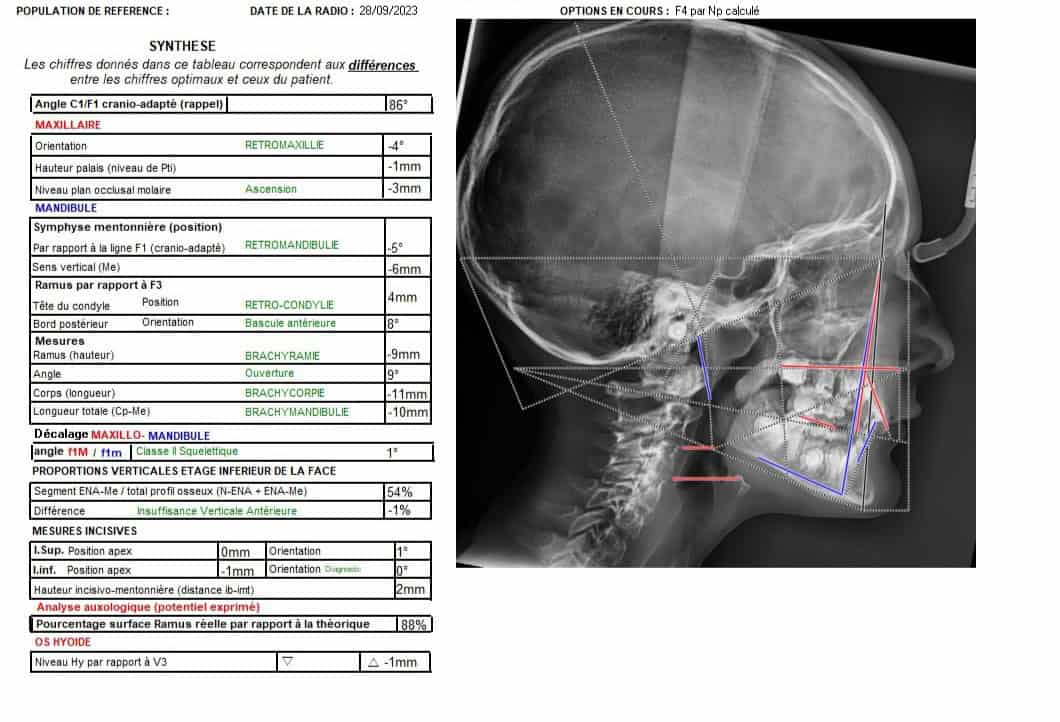

Exemple de cas :

les télécrânes pour l'orthodontie: